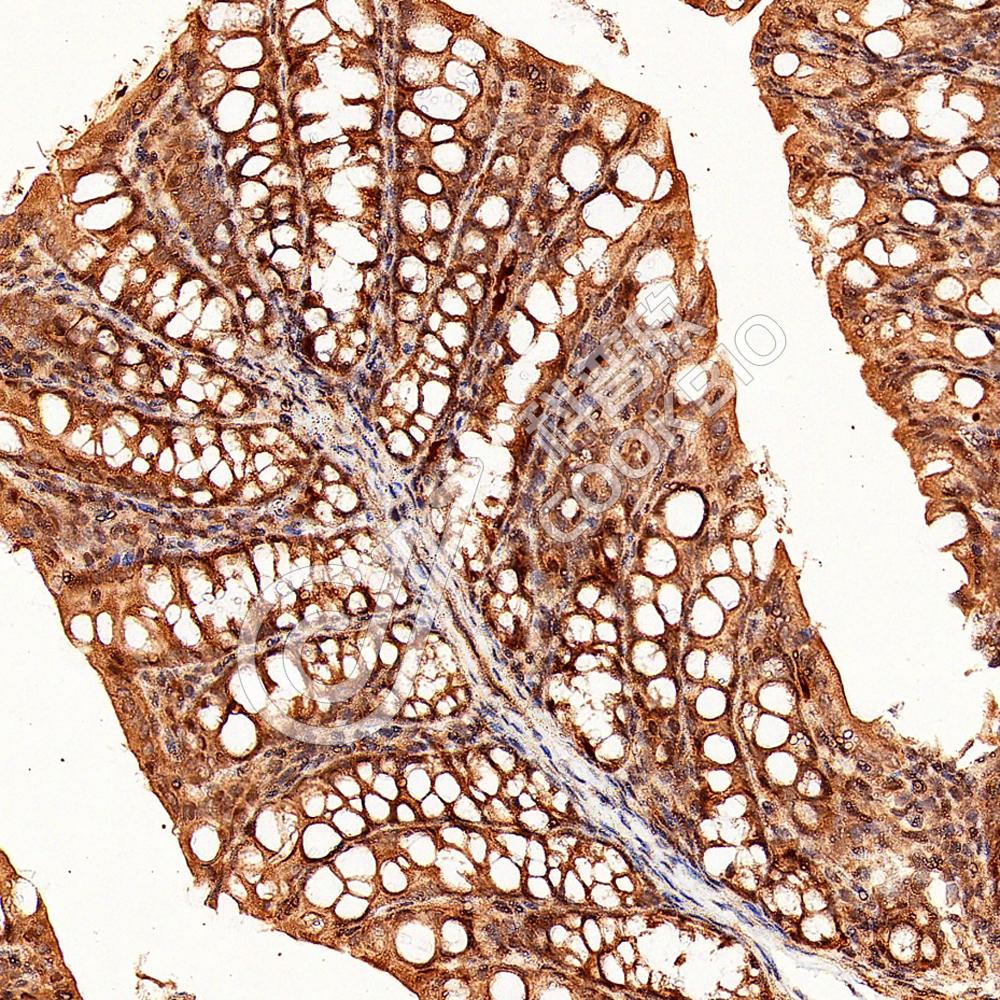

IHC检测ACP6蛋白(货号 K1343971).

样品: 小鼠结肠, 4%多聚甲醛 (货号KSG1101) 固定12-24小时.

抗原修复: 柠檬酸抗原修复液(干粉, pH 6.0) (KSG1201), 98℃, 20分钟.

—抗: 1: 1000稀释, 4℃ 孵育过夜.

二抗: S-vision免疫组化多聚二抗(山羊抗兔),即用型 (货号KB3906), 室温孵育20分钟.

样品: 大鼠结肠, 4%多聚甲醛 (货号KSG1101) 固定12-24小时.